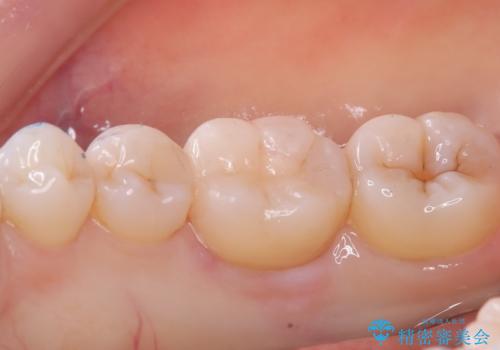

- 主訴:右下の奥歯がたまに冷たい物や甘いものでしみる

右下6番目の歯に大きめのう蝕を認め、形態の再現性を考えインレーでの治療となりました。

右下6の近心にう蝕が認められう蝕の範囲が大きかったため、歯冠形態の再現性の高いインレーでの修復とし、材質は審美性、清掃性に優れたセラミックを選択しました。